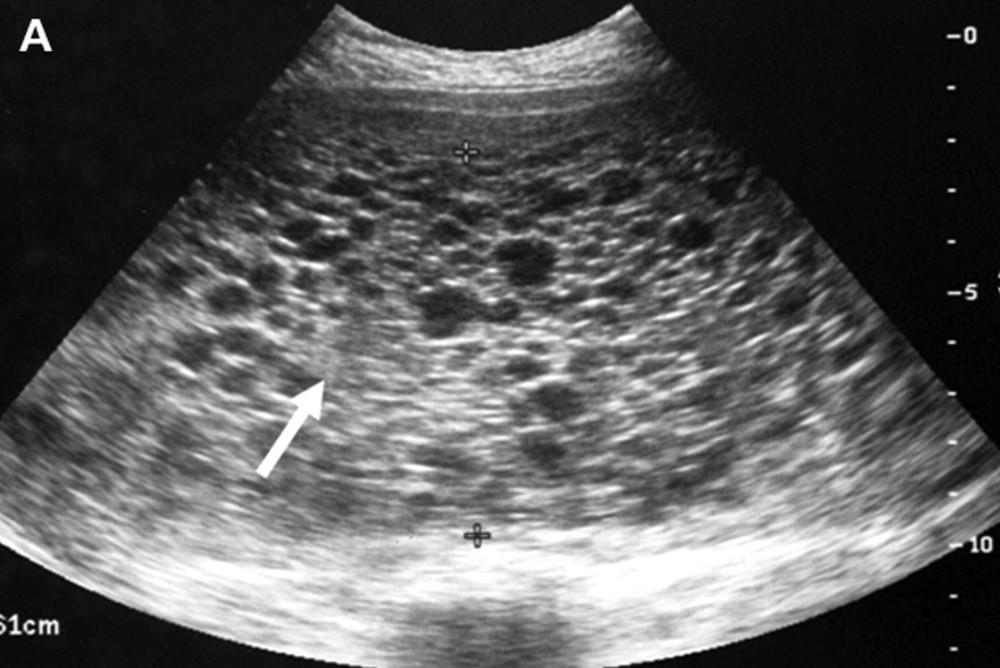

An Imgur user noticed something strange when his wife went to take an ultrasound test.

“Recently, we found out we were preggers. It was great news!” user 0tisdriftwood wrote, adding that his family would become a family of four “by one more heartbeat.”